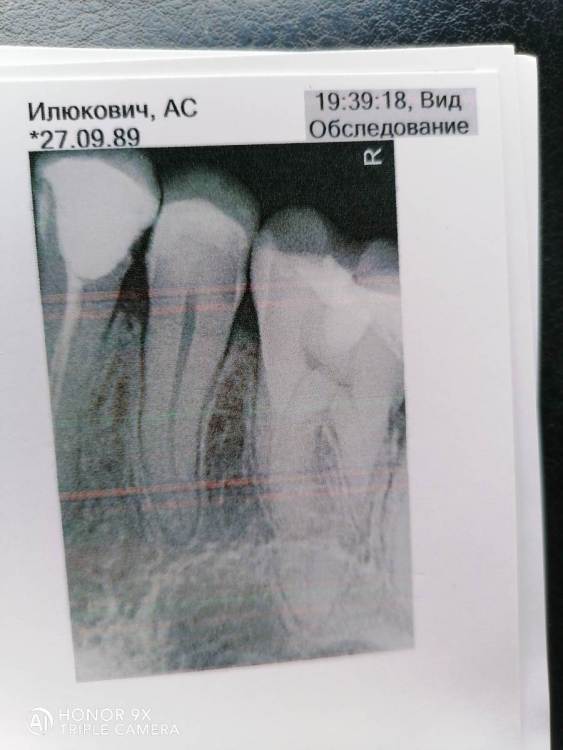

3 недели назад разболся зуб, пошла к стоматологу. По снимку ничего не увидели а предположили что пульпит и надо удалять нерв. Поставили лекарство и через два дня боль стала просто невыносимая. Побежала к стоматологу она сняла лекарство и предположила что

перешло в перидонтит. Половину каналов почистили, как оказалось нерв уже мертвый, но постоянно запломбирован каналы не рискнула, а дала возможность походить с временной пломбой. Зуб не переставал болеть.

Вчера пошла опять по острой боли. Сделали снимок там все хорошо. Приняли решение уколоть ультракаин и почистить каналы полностью. Неприятные ощущение даже под заморозкой сохранялись, но удалось пройти все каналы только услышала про 22 размер канала. Приехав домой боль стала ещё сильнее, но после обезболивающего прошла. Сегодня опять болит. Не могу понять почему. Стоит временная пломба в каналах. Стоматолог тоже не понимает в чем причина, но уверена что там ничего живого. При надавливании боль тоже есть и при простукивании. Страшно по итогу потерять зуб.